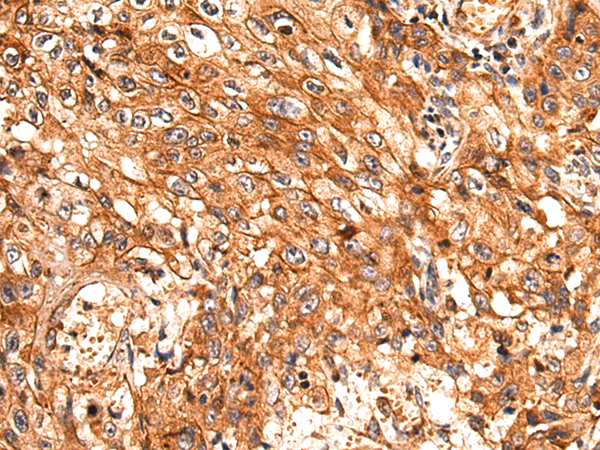

分类: 科研抗体货号: P01531别名: MORG1应用: WB,IHC反应种属: Human, Mouse, Rat

分类: 科研抗体货号: P01583别名: CI-30应用: WB,IHC反应种属: Human, Mouse

分类: 科研抗体货号: P01580别名: B8; CD14; CIB8; MC1DN13应用: WB,IHC反应种属: Human, Mouse

分类: 科研抗体货号: P01606别名: NS; E2IG3; NNP47; C77032应用: WB,IHC反应种属: Human

分类: 科研抗体货号: P01655别名: MPPB; P-52; MPP11; MPPP52; Beta-MPP应用: WB,IHC反应种属: Human, Mouse, Rat

分类: 科研抗体货号: P01604别名: CN1; CNI; CN-I; CN1A; CN-IA应用: IHC反应种属: Human, Mouse